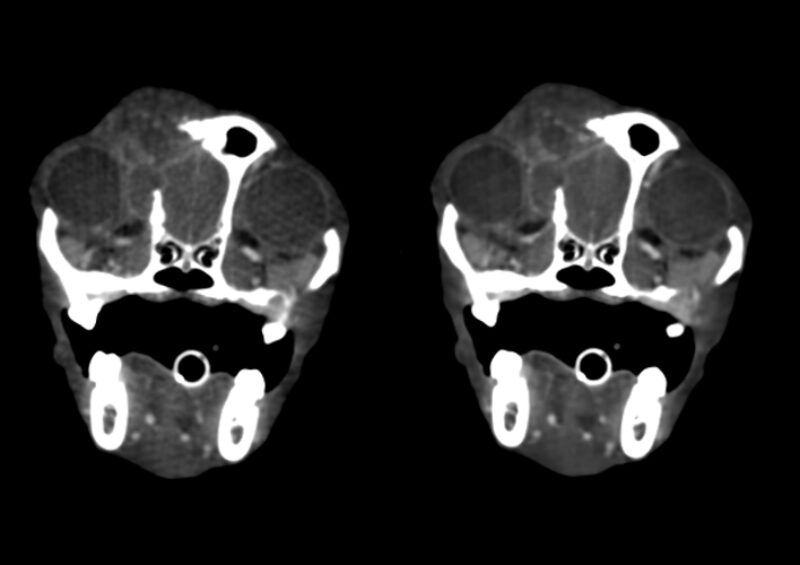

Kopf und Hals: Tumoren im und am Kopf lassen sich mit dem CBCT sehr präzise darstellen. Neben der exzellenten Beurteilung knöcherner Invasionen können auch Weichteilanteile zuverlässig abgegrenzt werden, was insbesondere für die präoperative Planung relevant ist. Kiefer- und Zahntumoren sowie komplexe dentale Erkrankungen profitieren weiterhin von der hohen Ortsauflösung des CBCT, die in diesen Bereichen einem klassischen Slice-CT überlegen sein kann. Bei brachycephalen Patienten hat sich das präoperative Dental-CT als Standard etabliert und ersetzt häufig eine Vielzahl konventioneller Dentalröntgenaufnahmen (Abb. 1 & 2).

Vergleichende Darstellung eines KI optimierten Kopfscans einer Katze mit einem destruktiven Tumor im Kopfbereich (links original, rechts KI gestützt).